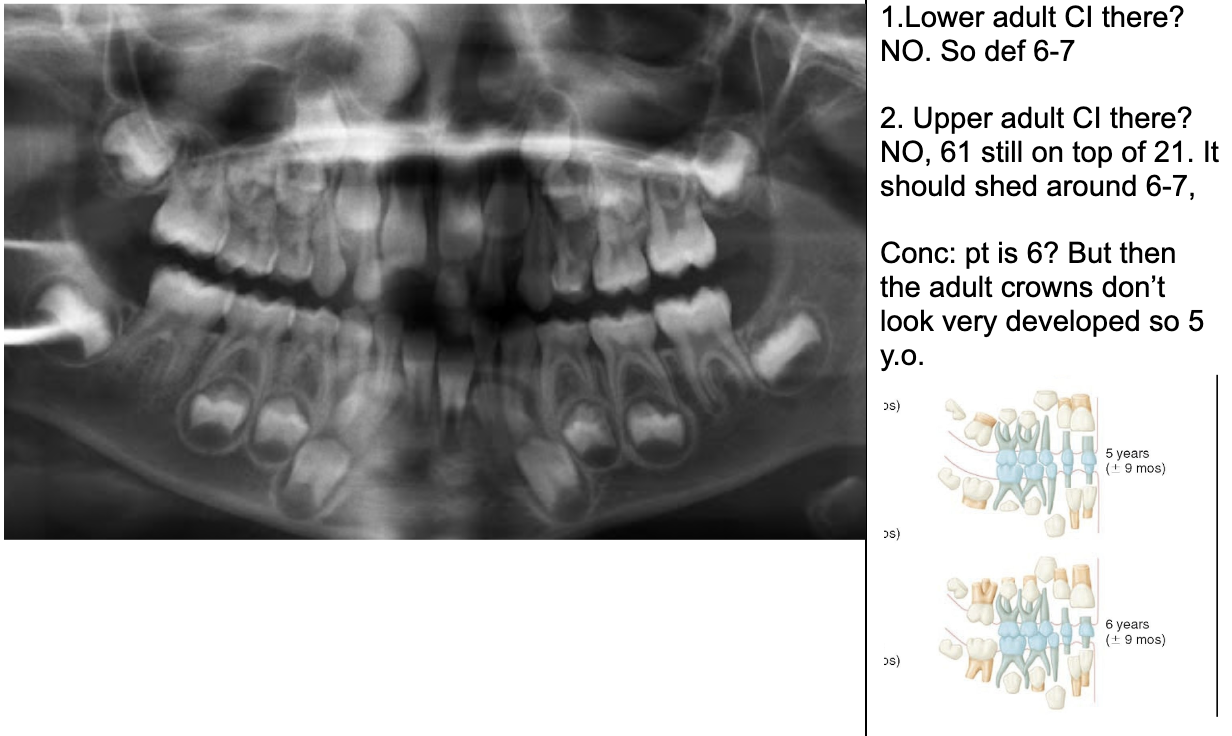

1.lower adult CI there? YES, so def 6-7

1. Upper Ad. Ci there? NO, so either 6-7 or under

Last molar crown not really formed so 6?

NOTE- THE 8’s - crown starts developing at 9 yo.